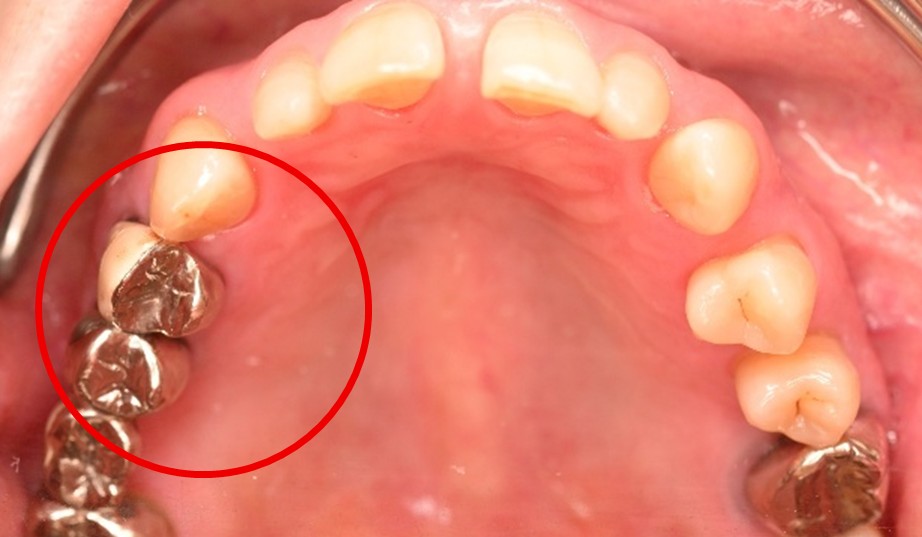

主訴

右上奥歯が、冷たいものにしみる。

治療内容

歯髄(神経および血管)まで到達する大きな虫歯でしたので、抜髄(歯髄を取り除く)をし、ファイバーコアをいれ、オールセラミック冠を被せました。

所感

現在、保険治療において、限定的ではありますが、大臼歯にも白い被せ物(プラスチック冠)ができるようになりました。しかし、実感としてプラスチック冠は、

- すり減りやすい。割れることがある。

- バイオフィルム(細菌およびそれから産生される副産物の塊)が付着しやすいので、歯周病および2次カリエス(被せ物と自分の歯の境目から再度虫歯になる)になるリスクが高い。

- 変色する。

という点を感じます。白い被せ物が保険の治療でできるという理由で、安易にプラスチック冠を選択し、割れたりすり減ったり、変色したらもう一度被せなおせばいいと考えるのであれば、一度立ち止まって考えてみてください。歯の量は、治療するたびに薄く少なくなり、歯根破折のリスクが高まります。もし大きな虫歯になってしまったら、最高レベルの根管治療をし、最良の被せ物であるオールセラミック冠を被せ、定期的にお口の中のクリーニングをし、同じ歯を2度と治療しないことが、歯を長持ちさせる最良の方法だと考えます。

オールセラミック冠(失活歯):¥104,500(税込)

Before

劣化したプラスチック冠

After